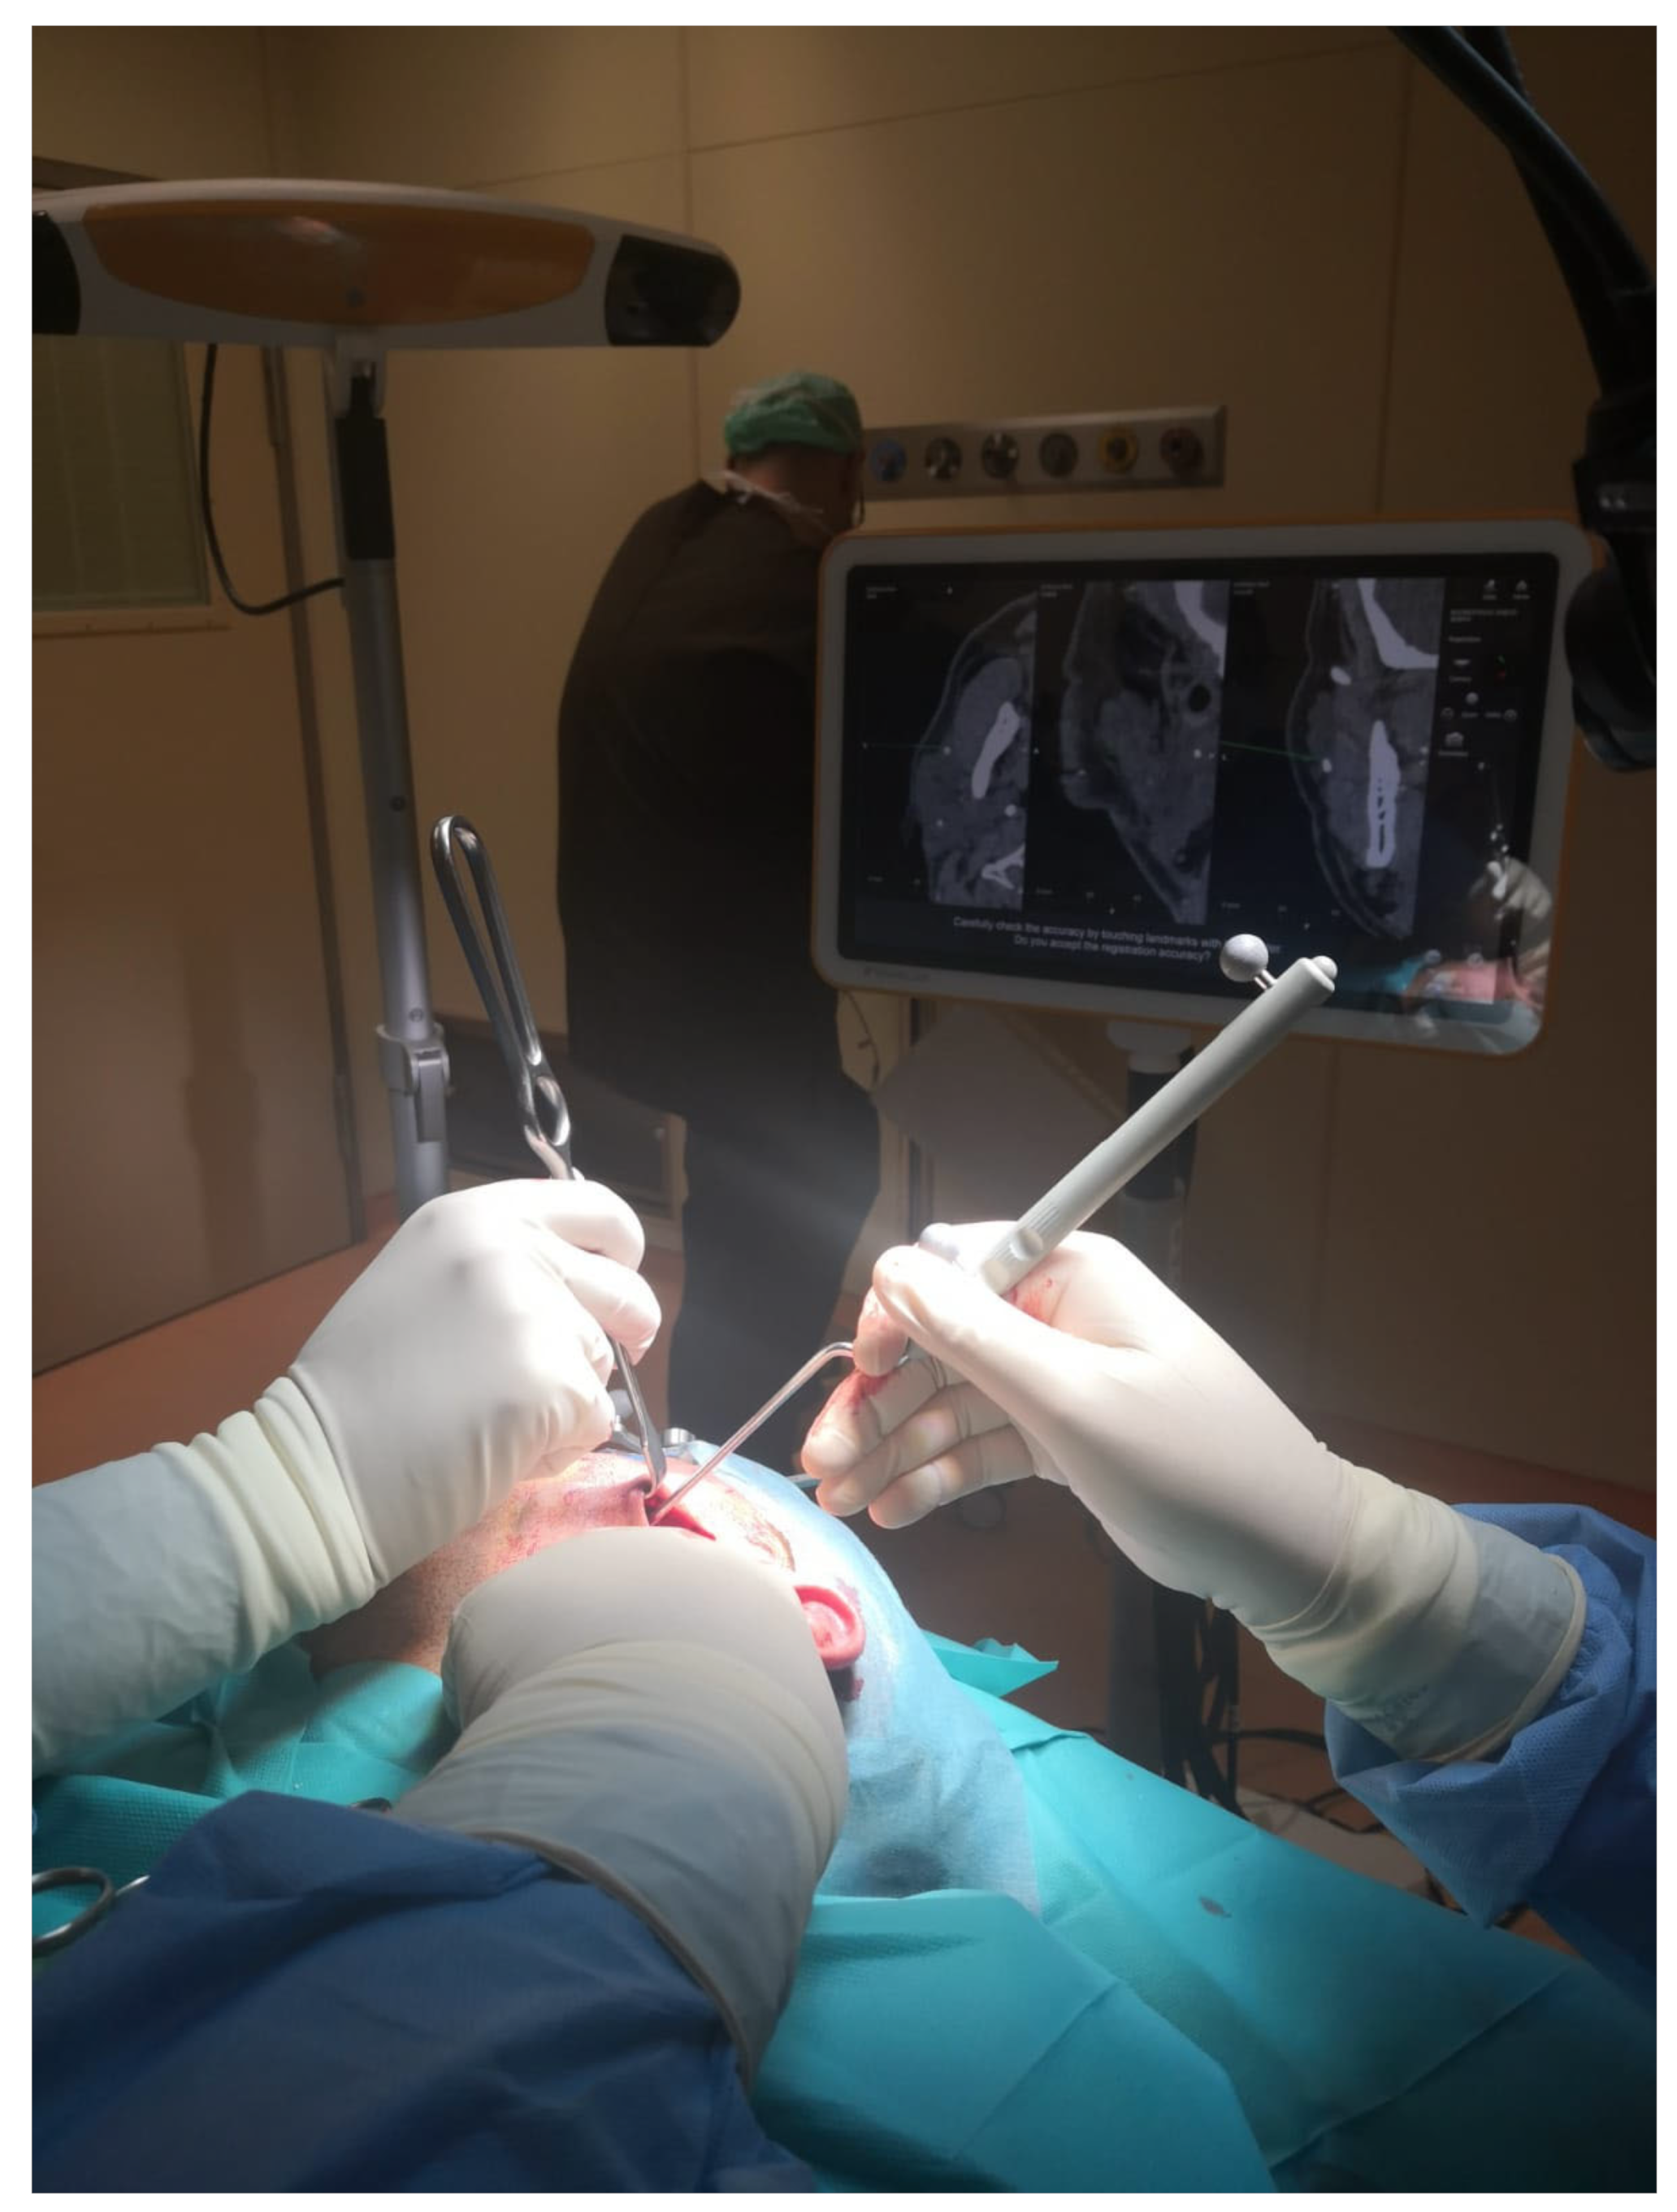

Figure 1). A reference star array was attached to a headband on the head of the patients and a laser pointer was used to record landmark points on the face. During surgery, axial, coronal, and sagittal CT images, previously uploaded and reconstructed, were displayed on a kick display (Brainlab, Munich, Germany) to track the navigation pointer. The optical-based navigation was used to locate the stone (

Figure 2) and its position marked on the skin surface (

Figure 3). A preauricular skin incision was made, a skin flap was raised, and a blunt dissection, guided by the navigation system, allowed the exposure of the parotid gland and the subsequent exact localization of the stone as visualized on the display (

Figure 4). A neurostimulator (Neuro-Pulse